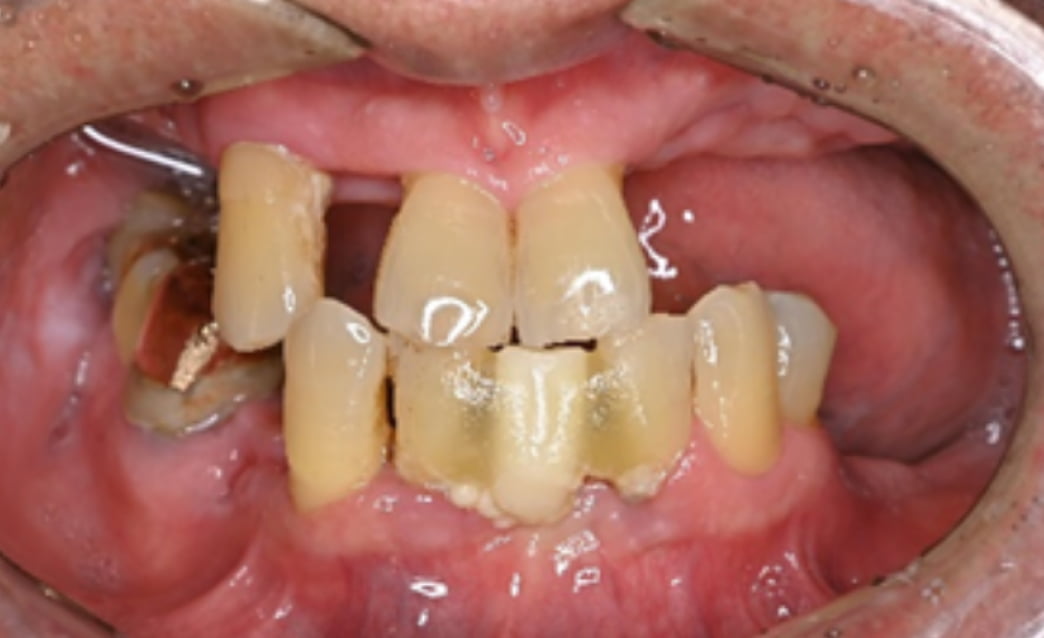

60代

Before

After

| 主訴 | 歯がぐらぐらする。 |

| 治療内容 | 下顎の残存歯は、歯周病が進行していたため全て抜歯をおこない、同日にインプラント埋入と仮歯の装着をしました。骨とインプラントが固定されるのを約3ヵ月待ち、型どりをして最終補綴を装着します。上顎にはフルデンチャーを使用し、快適に食事がとれています。 |

| 治療期間 | 6ヵ月 |

| 費用 | ¥3,586,000(税込み) |

| リスク・副作用 |

・外科処置が必要。コストがかかる。 |